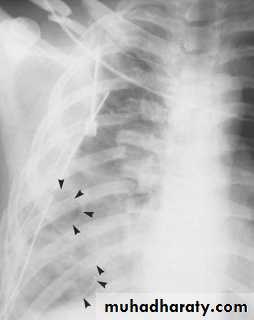

Posterior mediastinal mass

• Neurogenic tumours are by far the commonest cause of posterior mediastinal masses. Pressure deformity of the adjacent ribs and thoracic spine is often visible.